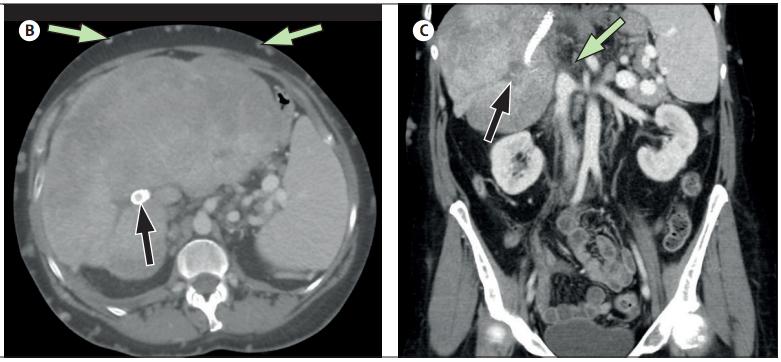

Se insertó una derivación portosistémica intrahepática transyugular (TIPS) proximal al trombo desde la porción hepática de la vena cava inferior hasta la vena porta principal, y el paciente comenzó la anticoagulación con warfarina. La tomografía computarizada repetida reveló el TIPS, venas prominentes de la pared abdominal (figura, B) y una vena hepática ocluida y vena cava inferior (figura, C).

(B) TC axial que muestra la derivación portosistémica intrahepática transyugular (flecha negra) y venas colaterales abdominales agrandadas (flechas de color verde pálido).

(C) Tomografía computarizada coronal que muestra la vena hepática ocluida (flecha negra) y la vena cava inferior (flecha verde pálida).